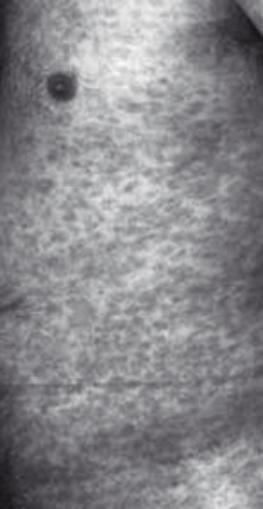

- II stadio: ä10 settimane dopo l¼infezione

febbre, mal di testa/articolazioni. Eczema „maculoso¾ poi papuloso (non prude

ma doloroso a pressione), ev. placche orali e perdita di capelli irregolare.

Facilmente da confondere con malattie dermiche: diagnosi sierologica!

1.9.2 Sifilide

II stadio: torace

1.9.2 Sifilide II

stadio: torace